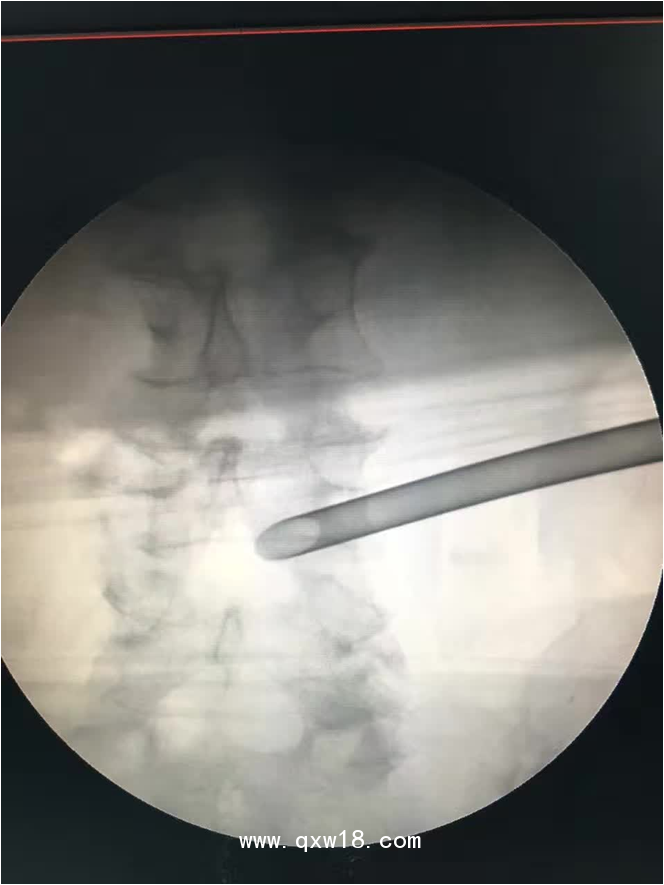

椎間孔鏡品牌椎間孔鏡椎間孔鏡技術(shù)椎間孔鏡培訓(xùn)產(chǎn)品說明:

portant; word-wrap: break-word !important;">椎間孔鏡手術(shù)圍手術(shù)期注意事項(xiàng):